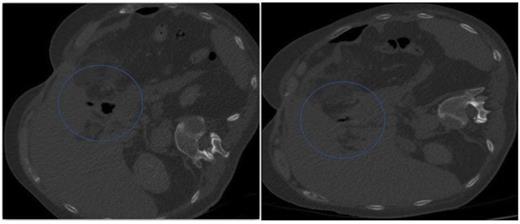

Follow up CT, with contrast both orally and through the T-tube, showed no evidence of ongoing leak from the pyloroplasty. The flanged T–tube satisfactorily plugged the hole through the anterior wall of the pyloroplasty, best demonstrated in the lateral decubitus position (Figures 7 and 8).

A follow-up CT demonstrating no evidence of on-going leak from the pyloroplasty & A follow-up CT demonstrating the flanged T-tube satisfactorily plugging the hole through the anterior wall of the pyloroplasty